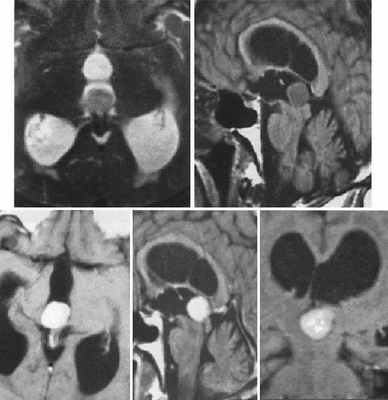

(а) МРТ, Т1-ВИ, сагиттальный срез: у мужчины 21 года с жалобами на головную боль определяется объемное образование, расположенное в пинеальной области, в сочетании с обструктивной гидроцефалией, расширением III желудочка и опущением миндалин мозжечка. Дифференциальный диагноз при диагностической визуализации должен проводиться между опухолью паренхимы эпифиза промежуточной дифференцировки (ОПЭПД), пинеобластомой и герминомой.

(б) МРТ, Т2-ВИ, аксиальный срез: определяется очень крупная опухоль паренхимы эпифиза промежуточной дифференцировки (ОПЭПД), распространяющееся в желудочковую систему. Обратите внимание на неоднородный на Т2-ВИ сигнал от объемного образования, в структуре которого отмечаются множественные кистозные очаги, что характерно для опухоли паренхимы эпифиза промежуточной дифференцировки (ОПЭПД).

(а) МРТ, постконтрастное Т1 -ВИ, корональный срез: у мужчины 24 лет определяется периферийный характер контрастирование крупного объемного образования пинеальной области.

При хирургической резекции была диагностирована опухоль паренхимы эпифиза промежуточной дифференцировки (ОПЭПД).

(б) МР-спектроскопия: у женщины 48 лет определяется повышение пика холина, снижение пика NAA и дублета лактата. Внешние признаки опухоли имеют слишком «агрессивный» для пинеоцитомы характер.

Герминомы редко встречаются у женщин среднего возраста. Визуализационные признаки наиболее характерны для опухоли паренхимы эпифиза промежуточной дифференцировки (ОПЭПД), хотя возможным диагнозом мог бы быть «папиллярная опухоль пинеальной области». При гистологическом исследовании была подтверждена опухоль паренхимы эпифиза промежуточной дифференцировки (ОПЭПД).